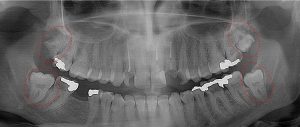

This 26 year old patient has all four 3rd molars present (circled). The upper right 3rd molar is badly decayed and the other three are partially erupted with signs of decay forming. Immediate extraction of all four is recommended.